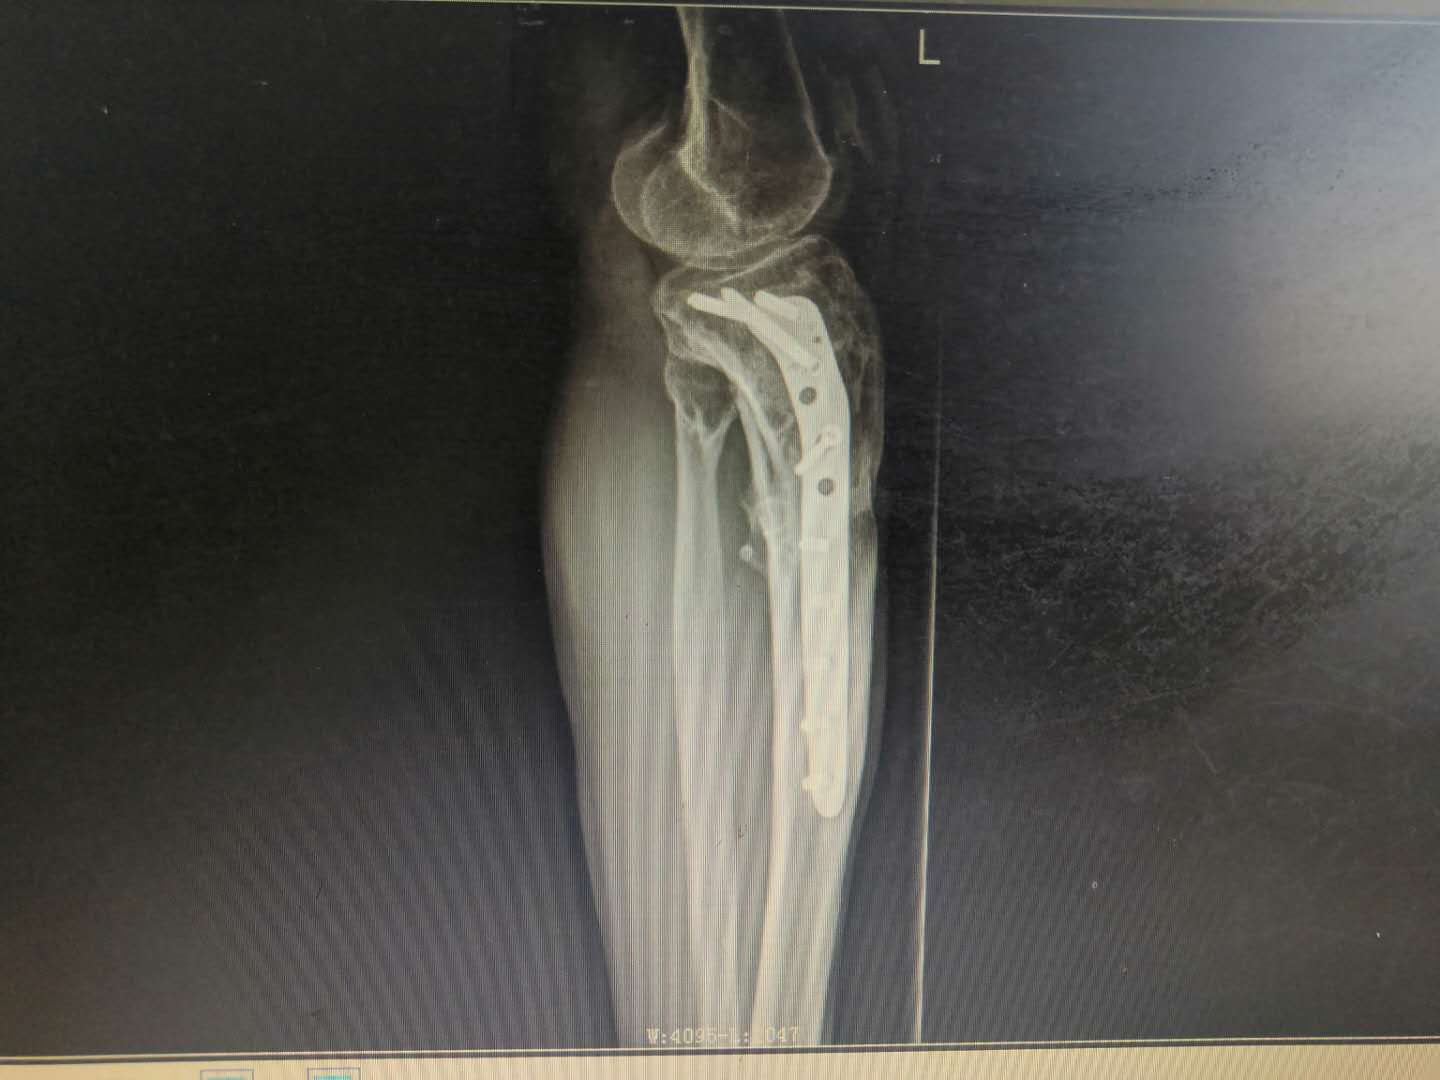

患   者:阳某,男,58岁。

主   诉:因左胫骨骨折术后伤口流脓5年,入院治疗。

现病史:自诉5年前因车祸致左小腿上段疼痛伴活动受限,在当地医院诊断为“左胫骨上段粉碎性骨折”,并行骨折切开复位内固定术,术后伤口未完全愈合,持续流出脓性液体,予伤口间断换药处理,伤口可愈合,但间断出现破溃口,其内流出脓液,现就诊于我院。

专科检查:左小腿中上段前外侧可见长约15cm纵行手术疤痕,周围部分皮肤色素沉着,可见两处皮肤溃口,挤压有脓性分泌物流出,皮下可扪及条状硬物,轻压痛,无异常活动,肢端血运感觉尚可。

辅助检查:血生化检查:血常规示白细胞12.35*109/L,血沉40mm/h,CRP正常,余未见明显异常。

影像资料:

1598324150170814.png1598324150719209.png

诊       断:

右胫骨上段慢性骨髓炎;右胫腓骨陈旧性骨折伴胫骨骨折术后内固定物滞留。

专家指导

针对此病例诊断及治疗方案,杨述华教授指导如下:

此病例诊断正确。

治疗时,需要将钢板取掉,如果骨头没长好,可以采用外固定防止再次骨折。在窦道口采用麻醉科硬膜外导管进行美蓝染色,顺着美蓝方向彻底清除慢性窦道。之后可以采取VSD负压引流,用抗生素冲洗伤口,再进行皮肤缝合;也可以直接缝合皮肤,缝合间距大一些。